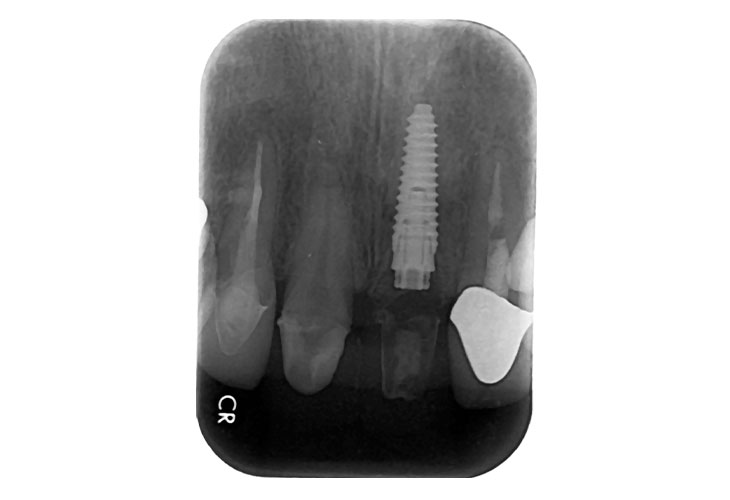

右上5番歯根破折 抜歯即時インプラント埋入

BEFORE

AFTER

| 金額 | ¥460,000(税抜) |

| 期間 | 約3ヶ月 |

| リスク | オペから6週までは過大な力がかかると骨の2次安定が得られないことがあるため、注意を要する。 |